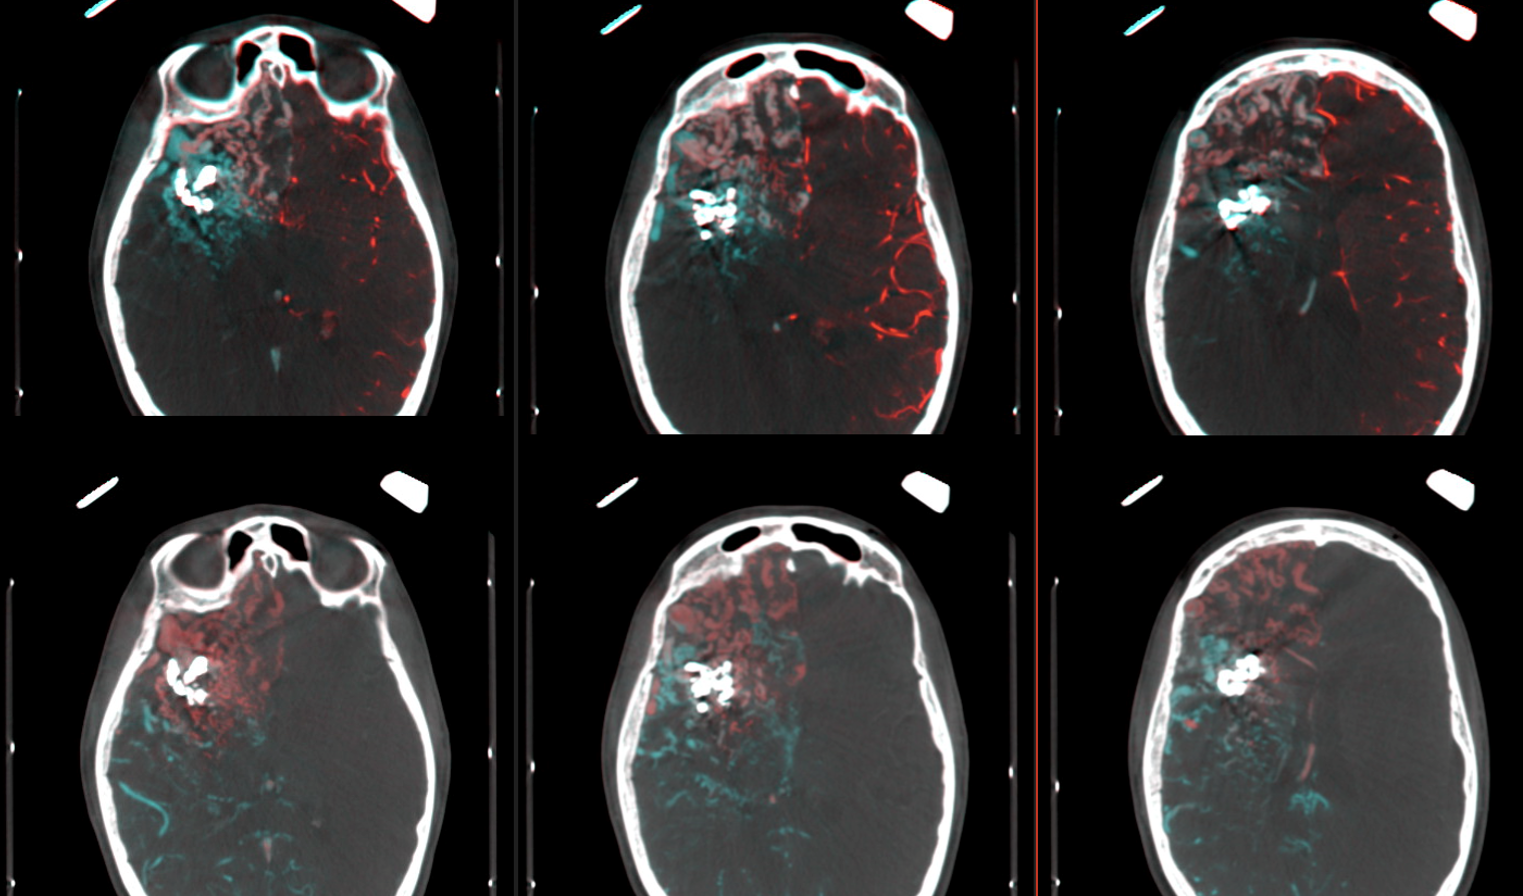

Here we see fusion of right (blue) and left (red) ICAs in the upper line and right ICA (red) and posterior circulation (blue) in the lower line. In white you see the cast of glue injected into some large AV shunts before GK.

Although this page is not about embo technique, or outcome, or whatever multiple clinical itch questions or comments you might have, the point to be made is that gamma knife does a terrible job with macro / large intranidal shunts. If there is any chance for it to work at all, close the big shunts sub selectively and maybe some of the vein (just not the whole vein…) and gamma knife the smaller vessels which are probably not even part of the nidus to begin with… It does work better.

Note that a cyanoacrylate was used here, not EvOH. That’s why anyone who wants to attack an AVM should know how to use glue. This job is for glue.